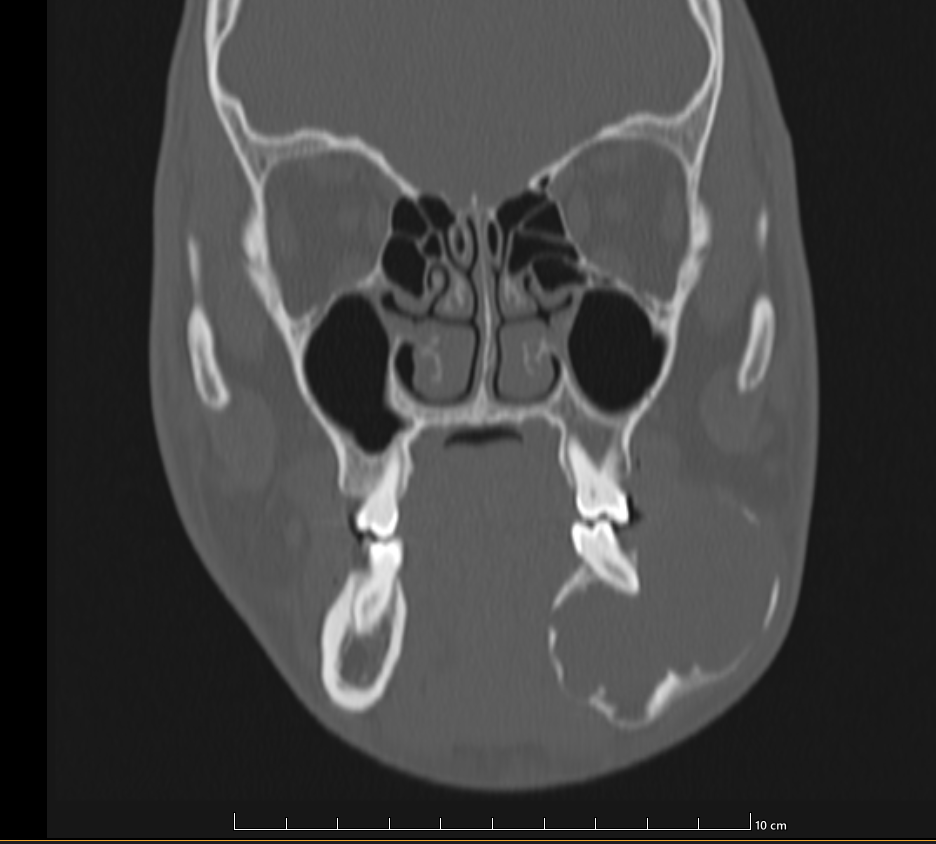

The bilateral maxillae, maxillary sinuses, their alveolar processes and hard palate are normal. The frontal, ethmoidal and sphenoid sinuses are normal. The cribriform plate and bilateral fovea ethmoidalis are normal.

Bilateral nasal bones are normal.

Nasal septum is mildly deviated towards left . Bilateral nasal turbinates are normal in size and attenuation.

Bilateral orbits, bilateral orbital walls and orbital contents are normal in attenuation. No hyperdense foreign body is noted.

Bilateral zygomatic arches are normal with no fracture or focal lesion. Bilateral pterygoid bones and pterygoid plates are normal.